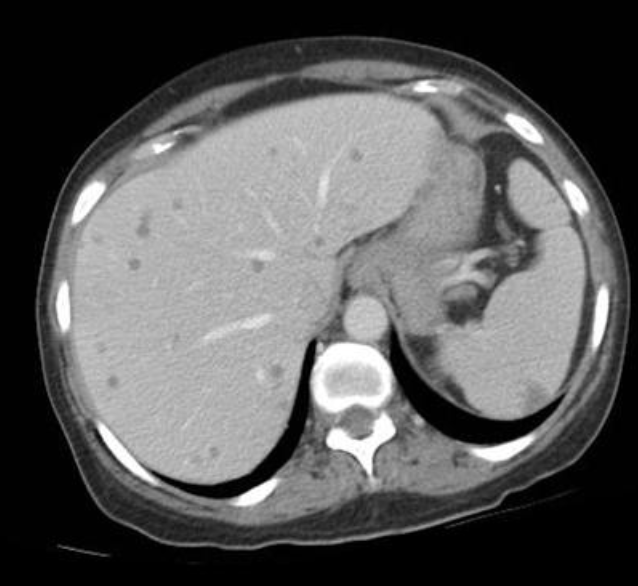

DDx multiple tiny hepatic hypoattenuating lesions

Hepatic infection: candidiasis

Ix: CT app.

Ex: immunocompromised pts., especially those w/hematologic malignancies + chemo.

Ix: CT: tiny hypoattenuating foci which may be rim-enhancing.